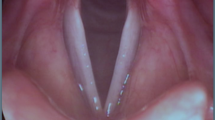

Clinical examination of voice disorders is challenging due to the small-scale, high-frequency oscillation of the vocal folds which is critical in the creation of an acoustic speech signal7. Therefore, advanced imaging techniques, such as videostroboscopy and high-speed videoendoscopy (HSV)8,9,10, are employed clinically and in research. The involved anatomy and an exemplary endoscopic image are shown in Fig. 1.

Numerous studies have shown significant relationships between different disorders and parameters computed from the segmentation data33,34,35, such as the cepstral peak prominence11. Typical signals derived from the glottis segmentation are the glottal area waveform (GAW)36, the vocal fold trajectories37 and the phonovibrogram38. Parameters computed from these signals bear the promise of a higher objectivity than many of the purely subjective metrics still being employed in the clinical routine36,39,40,41. Figure 1 shows an exemplary HSV frame and the corresponding segmentation.